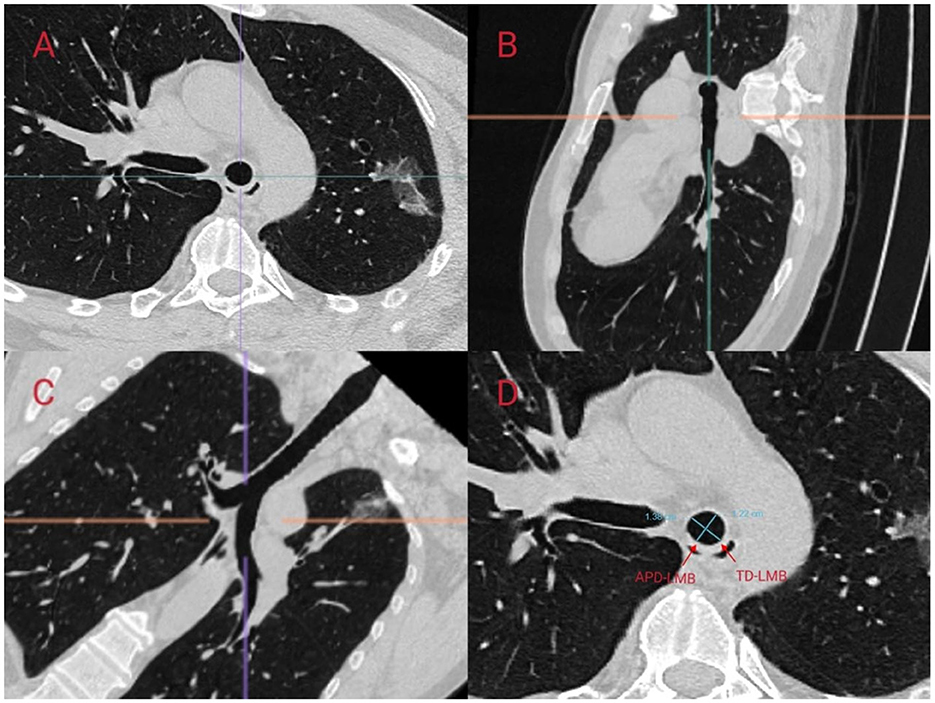

We referred to the ISO 16628:2022 standard for specific parameters of the double-lumen endotracheal tubes. The use of right-sided DLTs may lead to an increased incidence of complications, such as intraoperative hypoxemia and postoperative atelectasis, due to the potential obstruction of the orifice of the right upper lobe bronchus. In contrast, left-sided DLTs are generally considered to have a higher safety profile and are thus the preferred choice for thoracic anesthesia (11). Therefore, in this study, we aimed to predict the appropriate size for left-sided DLTs. In a study conducted by Mathew et al., the accuracy of predicting the size of left-sided DLTs by measuring the transverse diameter of the cricoid cartilage using CT was 97.5%, which was significantly superior to the 75% accuracy achieved using traditional methods based on height and gender (12). Other studies have indicated that the diameter of the left bronchus is also of significant importance in predicting the appropriate size of left-sided DLTs (13). In this study, we predicted the size of left-sided DLTs in patients by measuring the transverse diameter at the level of the cricoid cartilage (TD-C) on CT scans and calculating the equivalent circular diameter (ED-C) of the left bronchus. We followed the measurement methodology outlined by Shiqing et al. (14) in which anesthesiologists trained by radiologists utilized the MPR module of the Carestream PACS software to perform multiplanar reconstruction and measurements of the patients' trachea using axial, sagittal, and coronal slices. The inclination of the cricoid cartilage and left bronchus was adjusted to obtain strictly orthogonal slices (Figures 2, 3).

Figure 3. Scanning the left main bronchus (LMB) using Multi-Planar Reconstruction (MPR) in CarestreamPACS software to measure its diameter. MPR was performed using (A) axial, (B) sagittal, and (C) coronal slices. On the MPR image at 1 cm below the carina, the anteroposterior internal diameter of the left main bronchus (APD-LMB) and the transverse internal diameter of the left main bronchus (TD-LMB) were measured (D). The equivalent circular diameter (ED-C) was calculated using the formula for the perimeter of an ellipse, π[3(a + b) – ([a + 3b] [3a + b])], where a is the larger radius and b is the smaller radius, and the formula for the circumference of a circle.